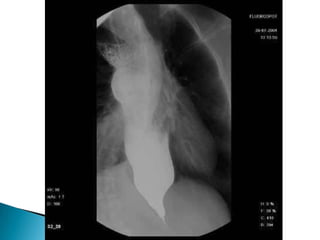

 Es unaenfermedad de la motilidad del esófago caracterizada por relajación incompleta del esfínter esofágico inferior y por la ausencia de la peristaltismo esofágica  Se produce por incapacidad del plexo mienterico para transmitir informacion lo que produce una relajacion receptiva del cardias  Esta lesión ocasiona megaesofago que almacena alimento el cual sufre putrefacción infección ulceración de la mucosa dolor retro esternal perforación y muerte del paciente